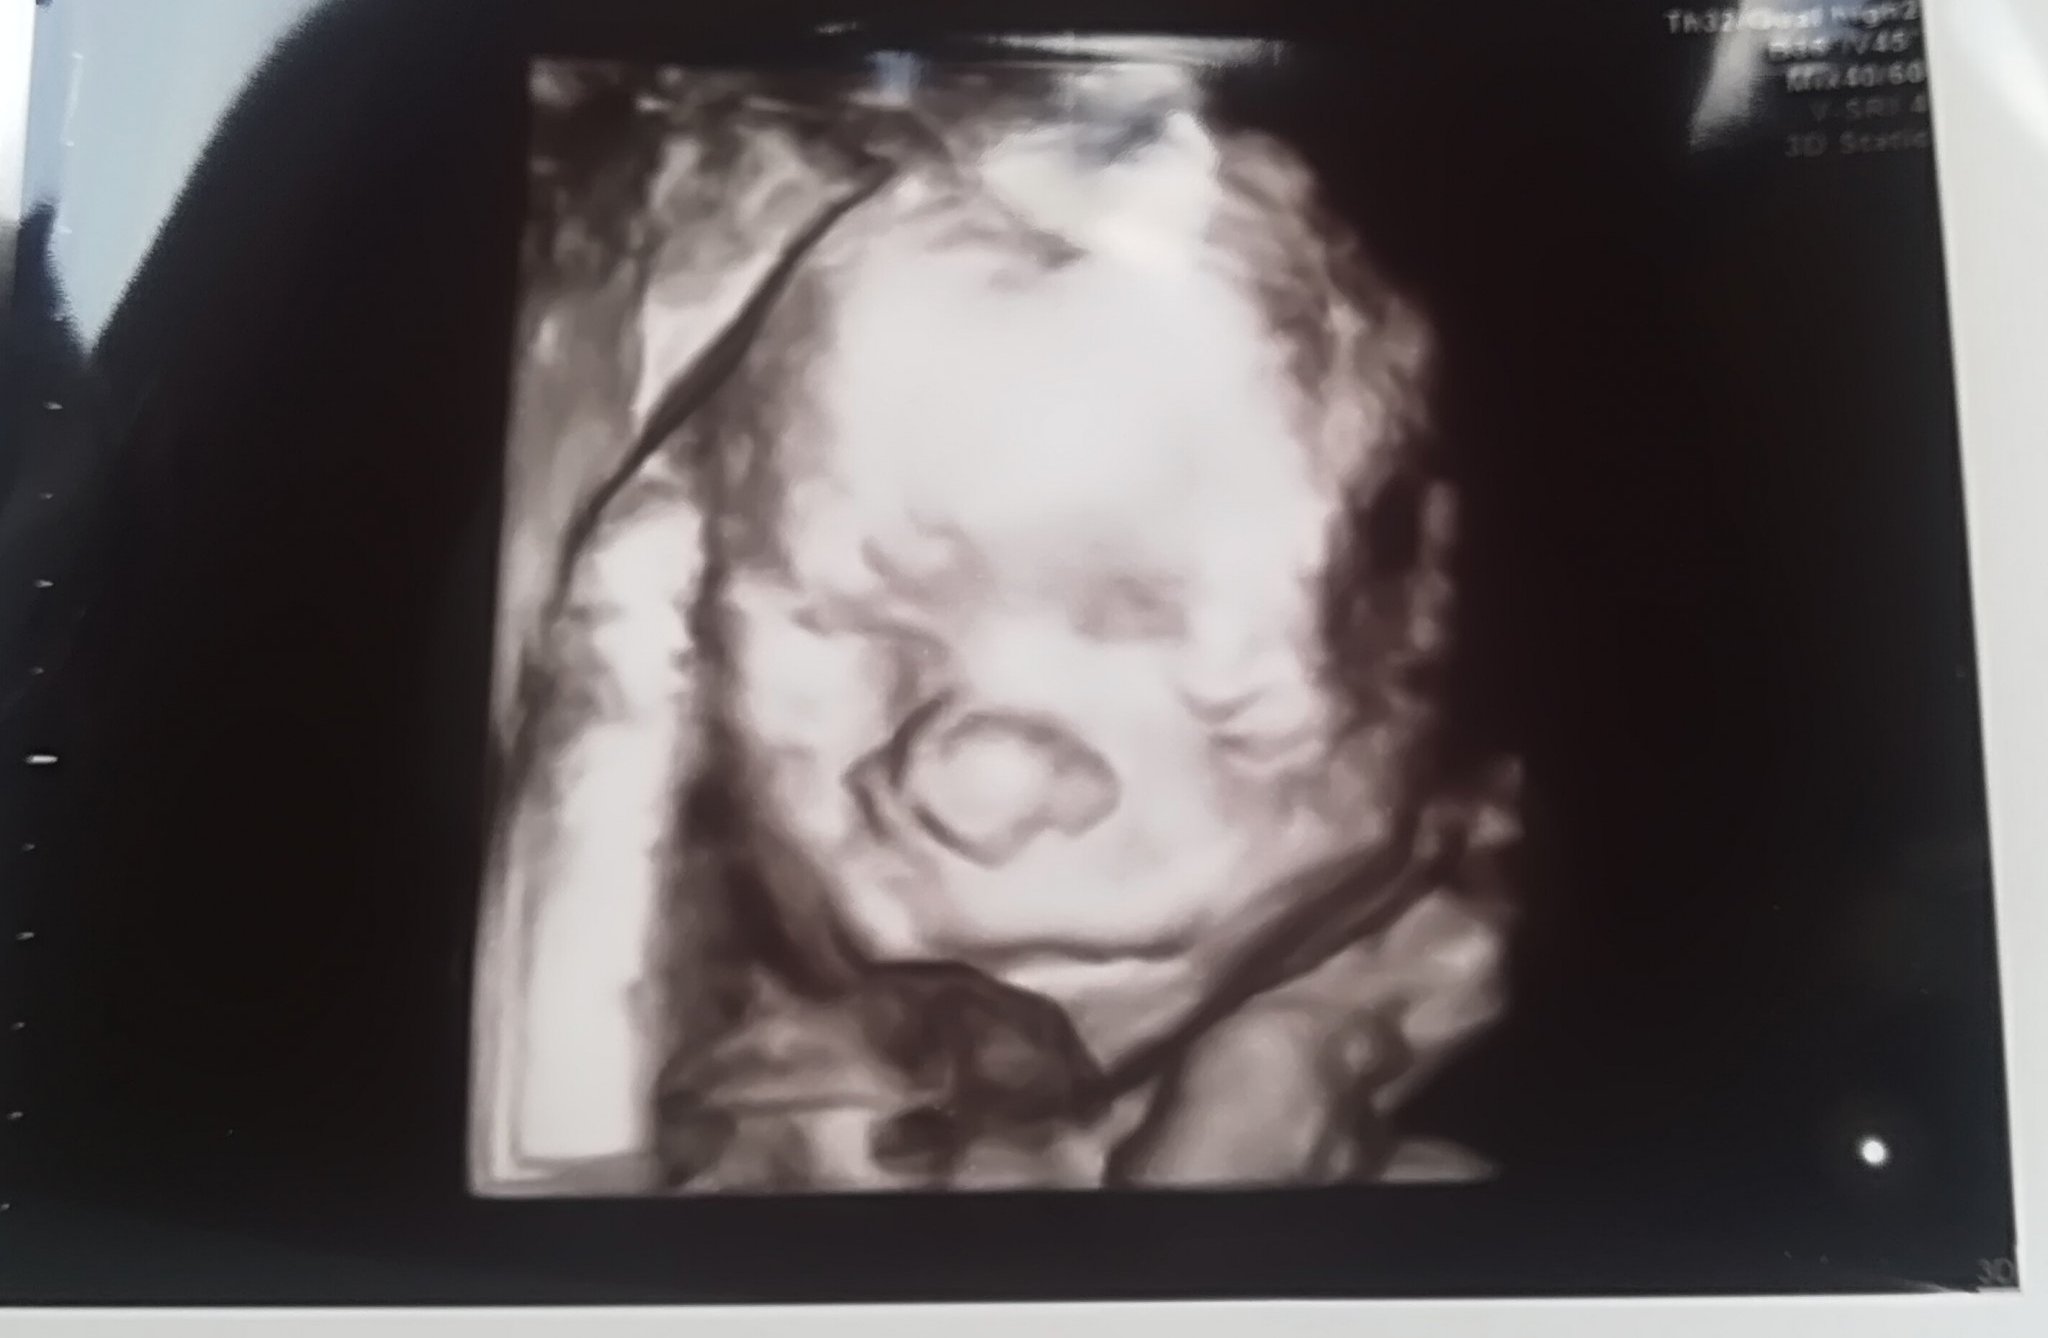

Днес мина втората ФМ.

Моето момиче е вече 435 гр. Hands Clap

Не спря да рита през целия преглед. Blush

Всичко й е наред - кости, мозъче, сърчице, док не вижда нищо притеснително.

Плацентата е вече висока, а не гранична.

Шийката ми е 3,3 см.

И не съм качила нищо, значи дотук 1,300 кг. в 21г.с.+3. Sunglasses